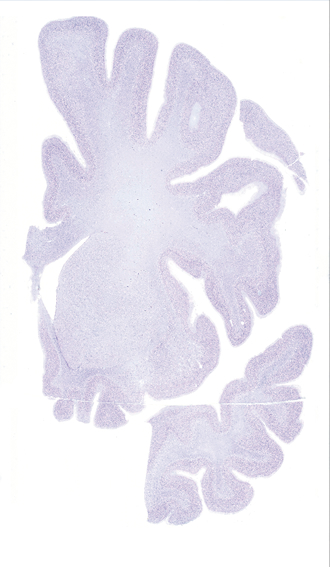

Hi-Resolution Sections · Cells (Nissl Staining) · Virtual Microscopy

Frontal sections (Nissl) from the Atlas Brain:

Slice ID:

r2-0205

Plate NR:

14

Position:

-10 mm